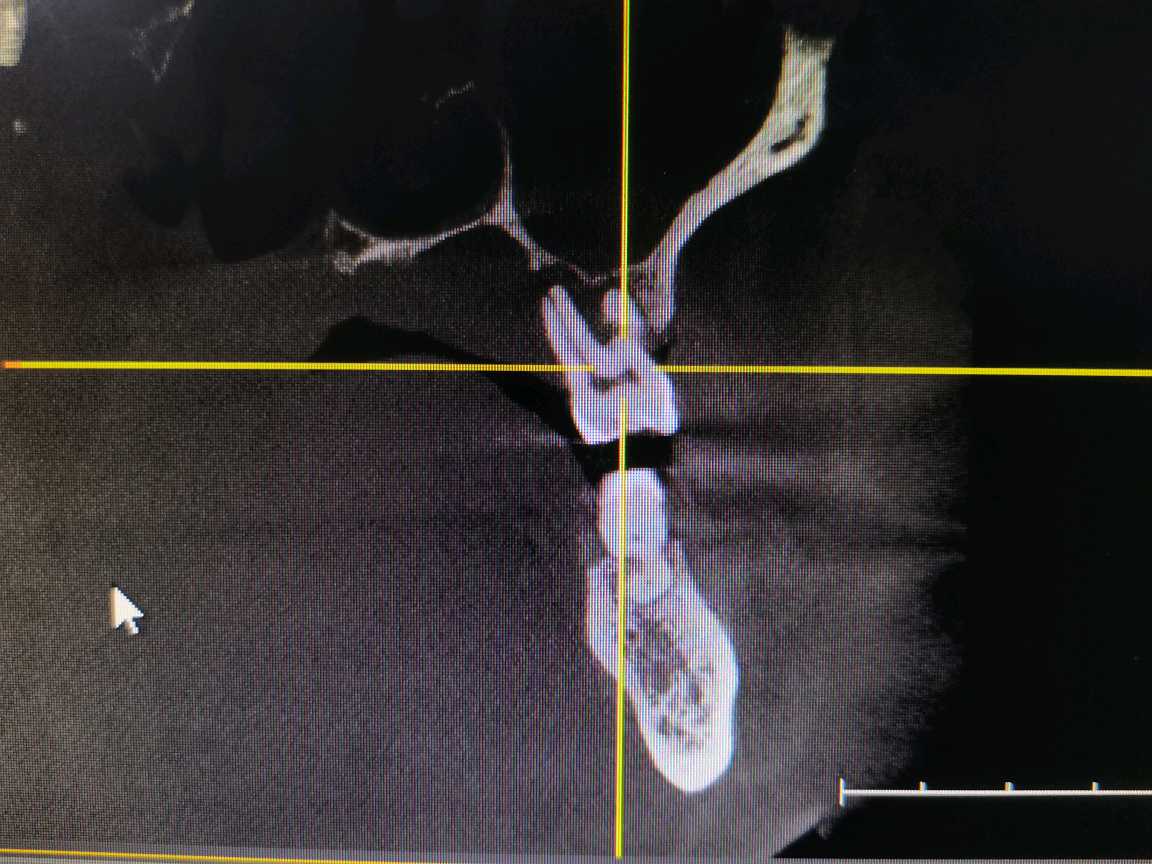

试尖片

术后根充片